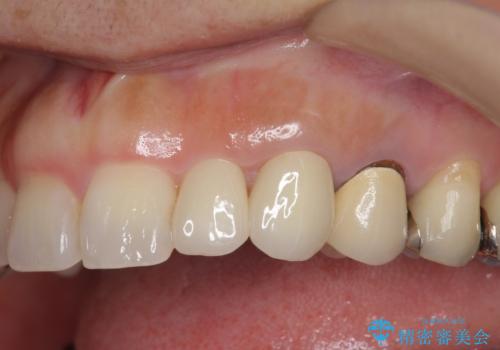

- 左上の前歯が小さく左右対称ではないのと、保険の前歯の被せ物のやりかえを希望して来院。

小さい前歯は、反対側と合わせた形にしました。

左右対称に仕上げることができ、治療には非常に満足していただきました。